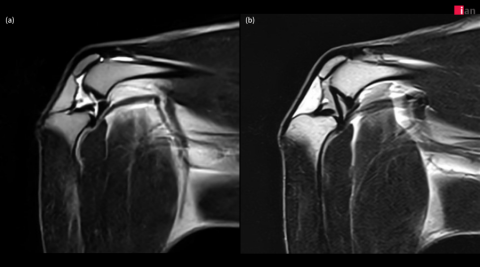

이안동물의학센터가 국내 동물병원 중 최초로 도입한 AI 기반 MRI 소프트웨어를 통해 무릎(Stifle joint) MRI 촬영 화질을 획기적으로 향상시키며 반려동물 정형외과 진단의 새로운 기준을 제시하고 있다고 밝혔다. 특히 이안동물의학센터는 이 소프트웨어로 복잡한 무릎 관절 내 구조물에 대한 세밀한 관찰이 가능해지면서 정확한 진단과 치료 전략 수립에 있어 큰 진전을 이루고 있다.

2023년 말부터 본격 가동된 이안동물의학센터의 AI 기반 MRI 소프트웨어는 딥러닝 알고리즘을 활용해 노이즈를 효과적으로 제거하고, 이미지 선명도를 대폭 향상시켰다. 특히 무릎 관절처럼 작은 구조물들이 복잡하게 얽혀 있는 부위에서 기존 영상 기법으로는 명확하게 파악하기 어려웠던 인대, 연골, 활액낭 및 인접한 근육 등의 세부 구조물까지 뚜렷하게 확인할 수 있어 정밀 진단에 큰 도움이 되고 있다.

이안동물의학센터는 정형외과에서 무릎 질환은 MRI로 진단하기에 가장 까다로운 분야 중 하나라며, AI 기술을 통해 MRI의 화질이 개선됨에 따라 십자 인대 파열, 연골 손상, 활액막 질환, 힘줄 질환 등 다양한 무릎 질환을 보다 빠르고 정확하게 진단할 수 있게 됐다고 설명했다.